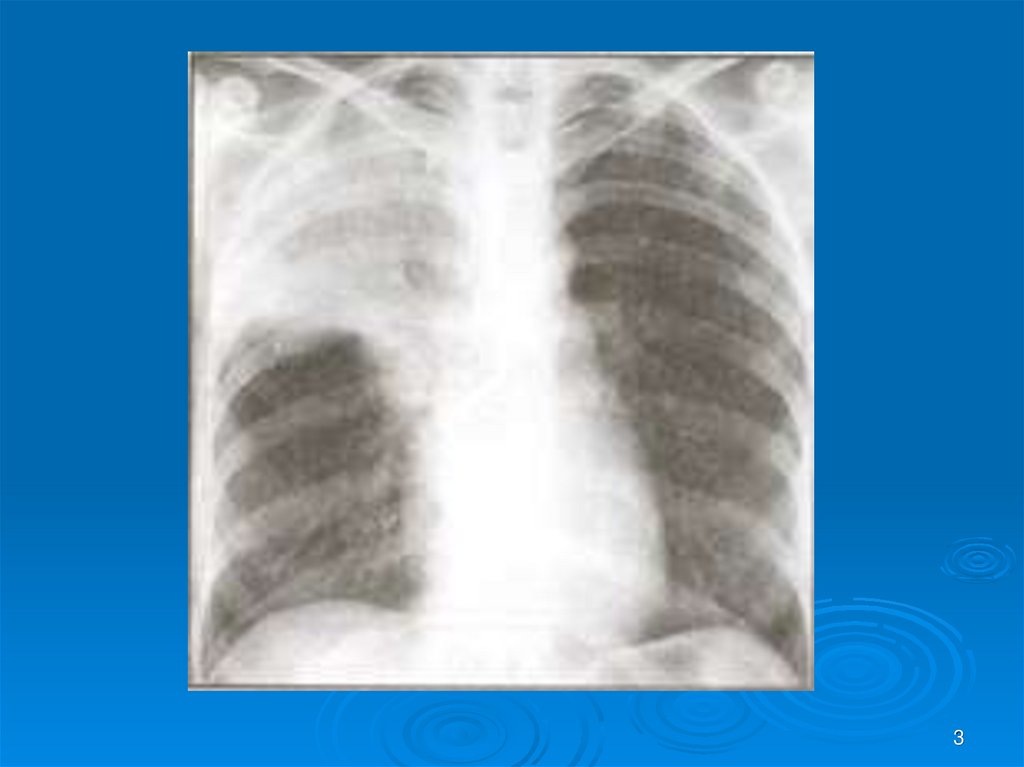

3.

3